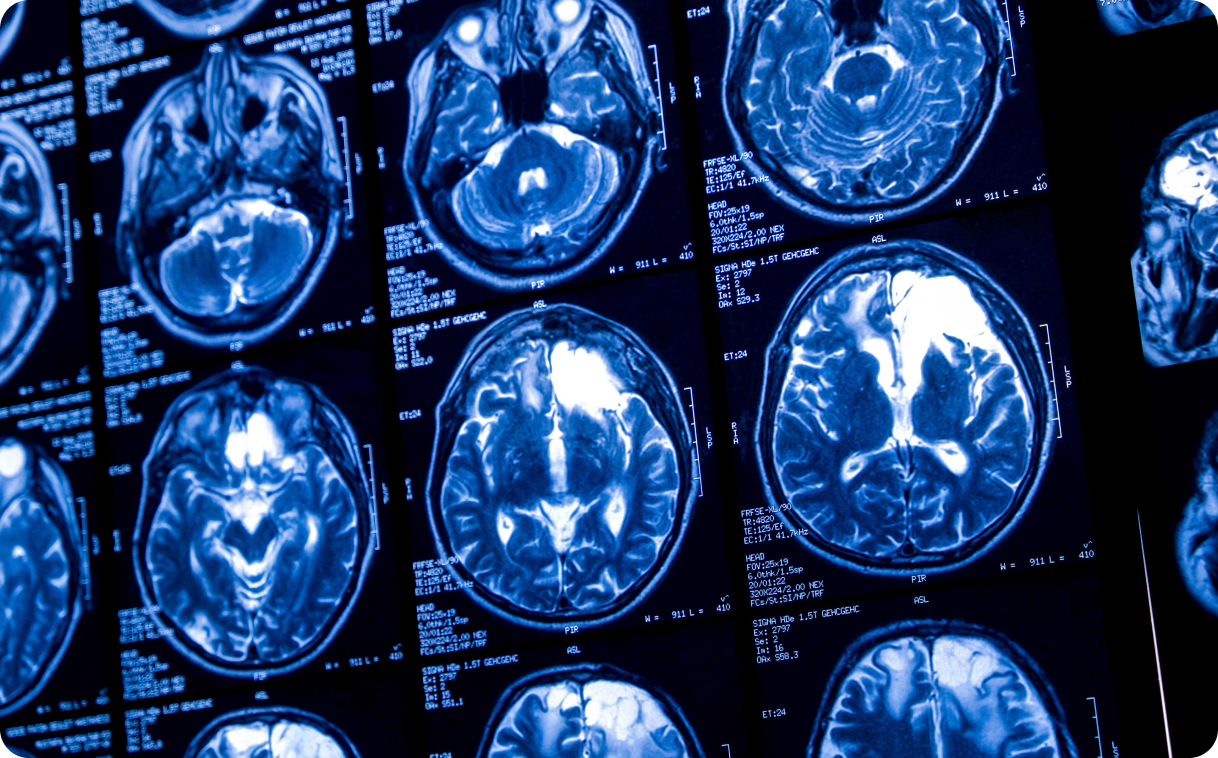

Опухоли мозга и дефицит серина

Слабое место некоторых глиобластом — особо агрессивных опухолей головного мозга — обнаружили американские учёные. Они выяснили, что многие глиобластомы поглощают аминокислоту серин из окружающей среды, а не синтезируют её самостоятельно. Эту метаболическую уязвимость можно использовать для замедления развития рака. В качестве эксперимента исследователи посадили мышей с опухолями на диету, исключающую серин и глицин (может превращаться в серин). При таком питании мыши с некоторыми видами глиобластомы выживали дольше по сравнению с теми, кто ел как обычно.

Потом учёные провели исследование с участием восьми человек, чтобы понять, как глиобластомы используют ресурсы организма. Испытуемым удаляли опухоли мозга и во время операции вводили сахарные молекулы, помеченные особым изотопом углерода. Анализ образцов опухолей и окружающей их ткани показал, что некоторые глиобластомы используют сахар из окружающей среды, например, базовых компонентов ДНК. Это способствует их бурному росту.

Глиобластомы быстро проникают в ткани мозга и почти всегда рецидивируют после лечения, которое обычно включает операцию, химиотерапию и лучевую терапию